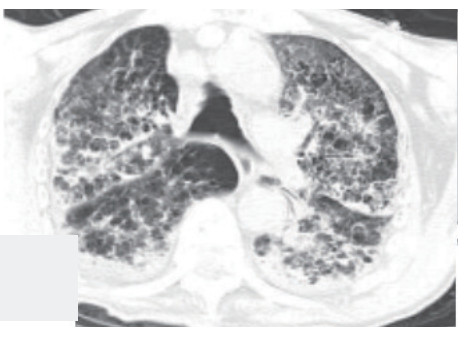

气管镜检查于当日10:20结束,在10:30患者在复苏醒过程中突发氧饱和度下降至60%,立即予纤支镜复检发现左下叶背段活动性出血,立即给予气管插管,局部去甲肾上腺素止血,垂体后叶素6 mg静注,甲强龙针80 mg静注,呋塞米20 mg静注等对症处理后,气管镜再次给予负压吸引,1 min后出血停止,患者氧饱和度恢复至82%。气管镜下未见明显出血。立即行胸部CT检查示两肺弥漫渗出影(见图 4),给予患者气管插管后转入ICU治疗。

| 两肺弥漫渗出,小叶间隔增厚 图 4 病例2气管镜术后(2020年5月8日)当天胸部CT |